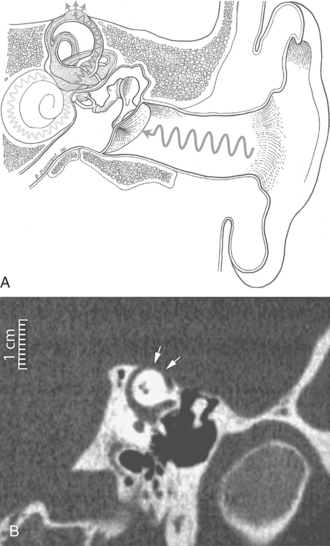

Definition and Overview.: Superior semicircular canal dehiscence syndrome is a syndrome of vertigo and oscillopsia induced by loud noises or by stimuli that change middle ear or intracranial pressure in patients with a dehiscence of bone overlying the superior semicircular canal. Tullio’s phenomenon (eye movements induced by loud noises) or Hennebert’s sign (eye movements induced by pressure in the external auditory canal) develop and often there is chronic disequilibrium.

Pathogenesis and Clinical Manifestations.: The dehiscence creates a “third mobile window” into the inner ear, thereby allowing the superior canal to respond to sound and pressure stimuli. The evoked eye movements in this syndrome typically align with the affected superior canal. Loud sounds, positive pressure in the external auditory canal, and the Valsalva maneuver can cause characteristic eye movements. A larger length of dehiscence overlying the superior canal (5 mm or greater) can lead to dysfunction in the affected canal when evaluated by responses to rapid head movements in the plane of the superior canal. Visual fixation can suppress the evoked eye movements.20 Fig. 38-15, A, shows the schematic representation of superior semicircular canal dehiscence; Fig. 38-15, B, shows the condition as seen on MRI.

Figure 38-15 A, In superior semicircular canal dehiscence syndrome, sound waves can excite the superior canal because the “third mobile window” created by the dehiscence allows some sound pressure to be dissipated along a route through the superior canal in addition to the conventional route through the cochlea. B, CT scan demonstrating dehiscence (arrows) of the superior canal. (From Cummings CW, Haughey BH, Thomas R, et al: Cummings otolaryngology: head and neck surgery, ed 4, St Louis, 2004, Mosby.)